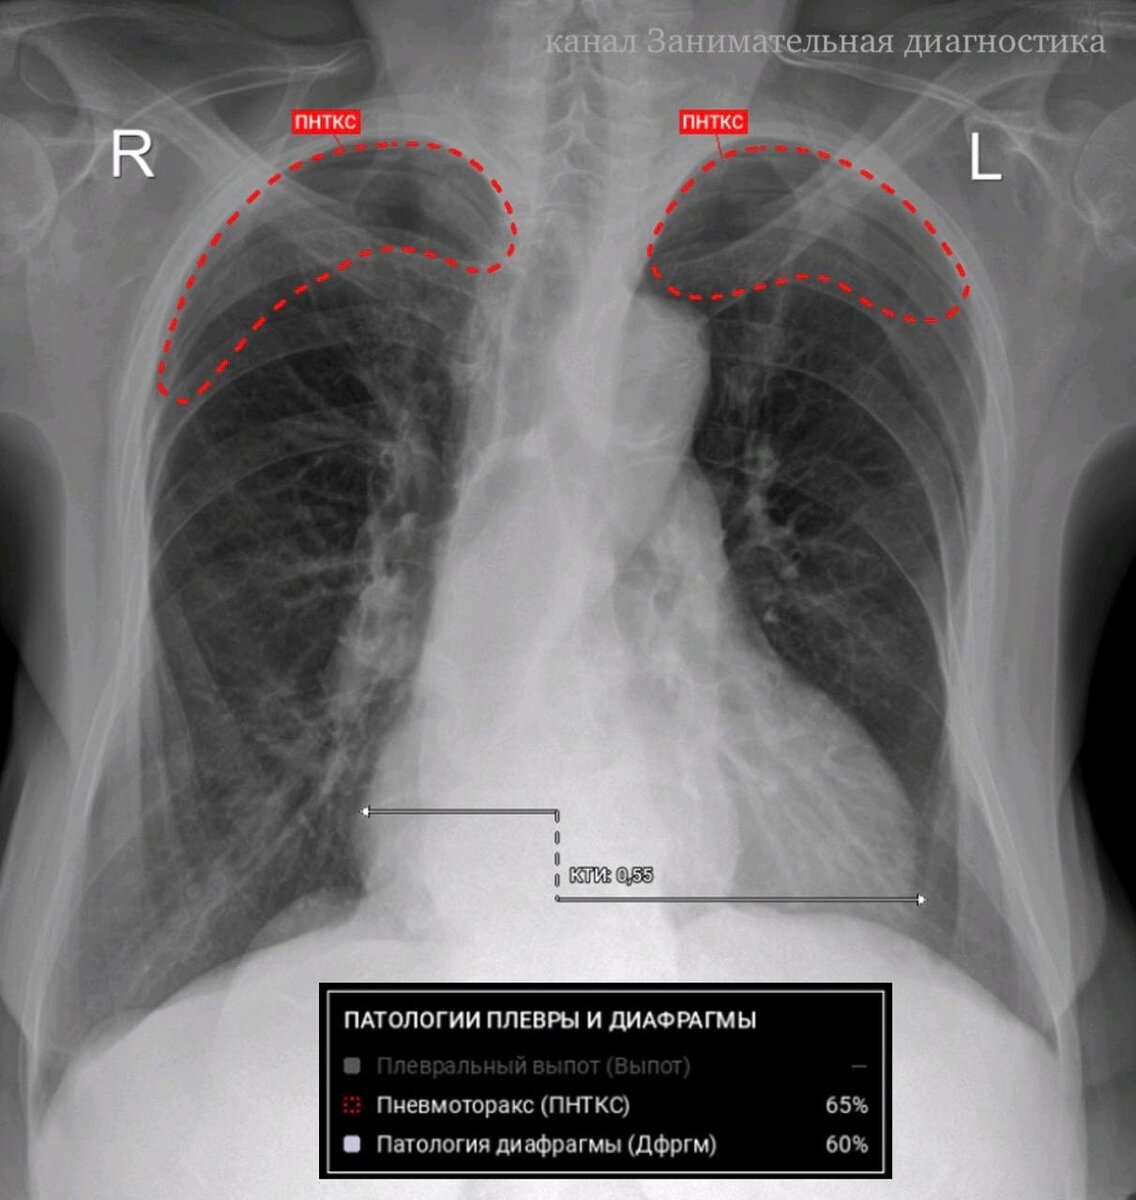

А теперь, дамы и господа, позвольте представить реальный, свежий пример работы ИИ из практики. Без всей этой маркетинговой болтовни.

Взгляните на снимок.

заключение и разметка ИИ

Ничего не подозревающему пациенту машина внезапно выставила… ДВУХСТОРОННИЙ ПНЕВМОТОРАКС (это когда в плевральных полостях свободный газ и нужно немедленно делать прокол, чтобы этот газ выпустить, иначе лёгкие не могут расправиться).

И всё бы ничего. Вот только на снимке - НОРМА (за исключением расширенного сердца). Лёгкие расправлены, без патологии!

Кто-то может предположить, что это какая-то случайная техническая ошибка, связанная с низким качеством изображения и т.п. Но.. нет. Данный снимок отличного качества. Представьте, если снимок будет нечётким? а это часто бывает, особенно у тяжелых лежачих пациентов.